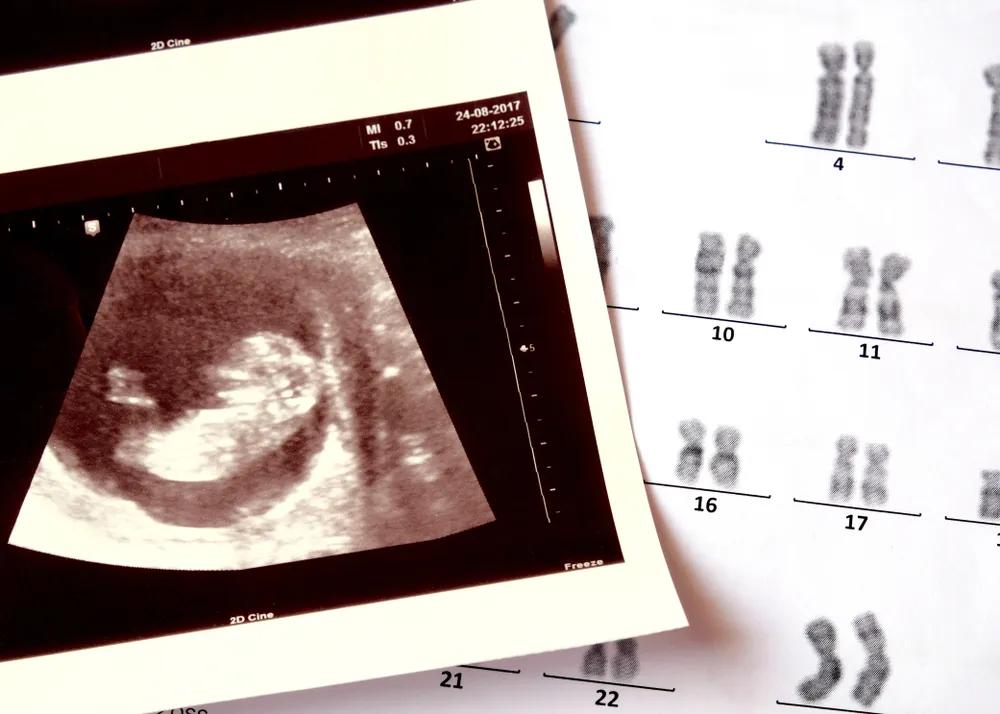

当生育不能自然来临,一些人被下了「不孕」的诊断,当生育的环节需要医学的介入、付出额外努力时,可能,我们才会重新审视生育本身,窥见「成为母亲」可以是一个选择,看到女性需要为生育本身承担的职责与焦虑。

很多生育障碍的夫妇,寄希望于试管等生殖技术,来改变生活状态,但技术的不确定,让焦虑卷土重来,很多女性被身体受创与生殖焦虑反复拉扯。

曾纪琪夫妇正在尝试试管婴儿。

根据中国人口协会、国家计生委联名发布的《中国不孕不育现状调研报告》显示,中国的不孕不育发病率在 12.5%~15% 左右,患者人数超过 4000 万,占到全部育龄人口的 12.5% 。

为了尽可能排除那一点点因素,曾纪琪和黎晓都选了更明确的方案 —— 试管。